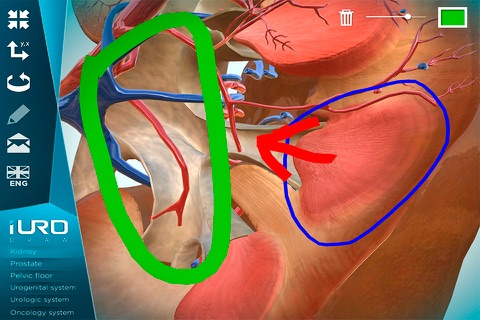

iURO Draw app for iPhone and iPad

Developer: URO Developments

Anatomical models on which to paint with different colors and to explain to patients and students various diseases and treatments.